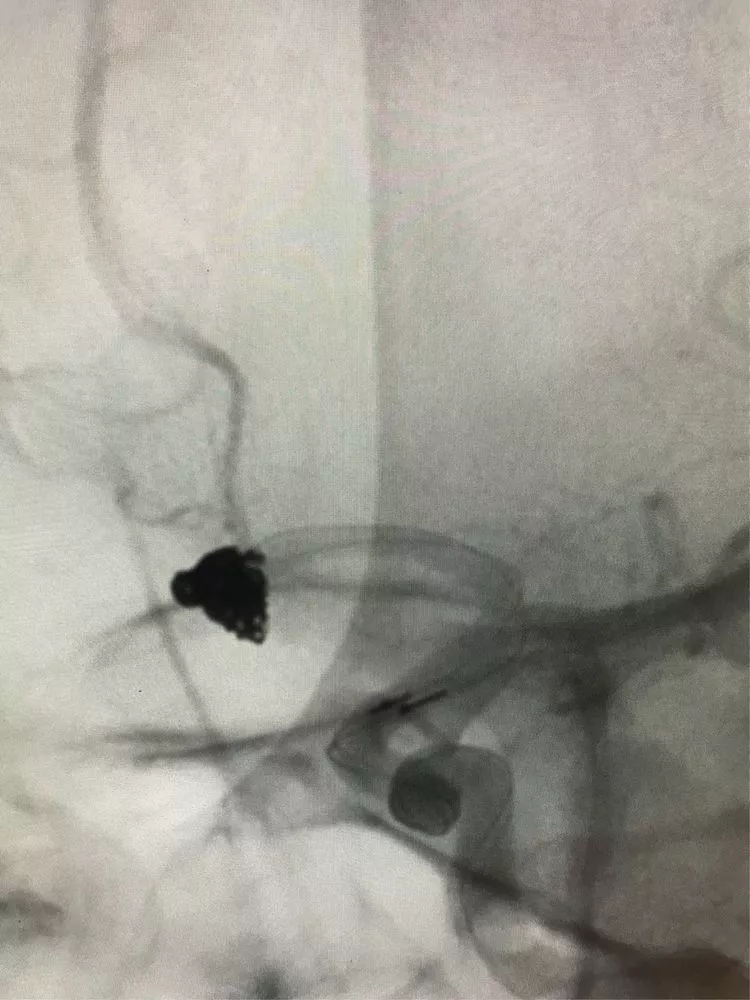

最后的影像。(瘤颈与前交通的切线位,没有弹簧圈突入前交通。)

正位,看双侧大脑前A2。

侧位。